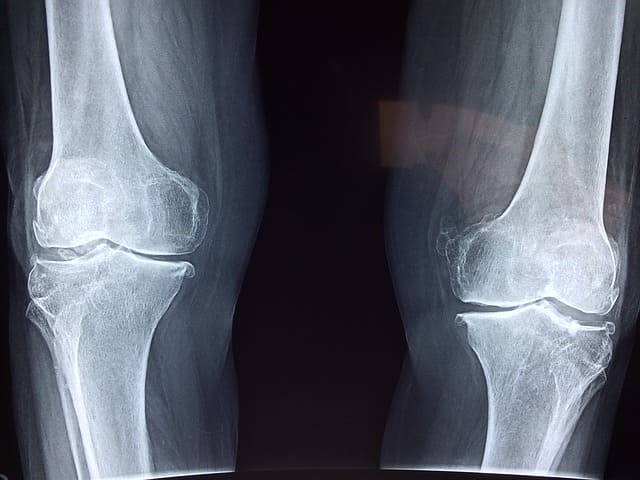

슬개골 연골 연화증의 진단은 주로 임상적인 평가와 영상 검사를 통해 이루어집니다. 의사는 환자의 증상과 병력, 신체 검진을 통해 초기 평가를 실시합니다. 추가적으로, 엑스레이, MRI, CT 스캔 등의 영상 검사를 통해 슬개골과 무릎 관절의 상태를 확인할 수 있습니다. 이러한 진단 과정을 통해 슬개골 연골 연화증의 정확한 진단이 가능하며, 적절한 치료 계획을 수립할 수 있습니다.